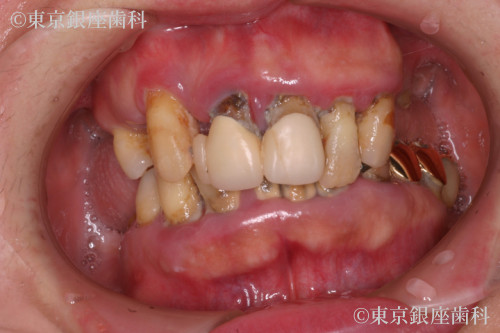

Before

重度歯周病で上下インプラントを選択。治療後、顔の赤みが改善し噛む機能も回復。補綴の形態修正も行い自然で快適な仕上がりに。

疾患 歯周病